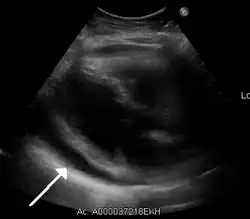

Ultrasounds showing a pericardial effusion in someone with pericarditis

-

A pericardial effusion as seen on CXR in someone with pericarditis

The diagnosis of tamponade can be confirmed with trans-thoracic echocardiography (TTE), which should show a large pericardial effusion and diastolic collapse of the right ventricle and right atrium. Chest X-ray usually shows an enlarged cardiac silhouette ("water bottle" appearance) and clear lungs. Pulmonary congestion is typically not seen because equalization of diastolic pressures constrains the pulmonary capillary wedge pressure to the intra-pericardial pressure (and all other diastolic pressures).